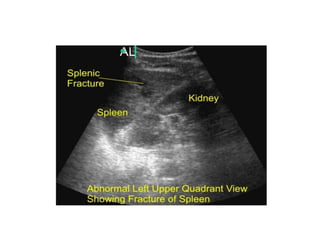

SPLENIC INJURY

• Most common intra- abdominal organ to injured (40-55%)

• 20% of splenic injuries due to left lower rib fractures

• Commonly arterial hemorrhage

• Conservative management :

-Hemodynamic stability

- Negative abdominal examination

-Absence of contrast extravasation in CT

- Absence of other indication of Laprotomy

-Grade 1to 3 (Subcapsular Hematoma ,Laceration <3 cm)

Monitoring

• Serial abdo. Examinations & Haematocrit are essential

• Success rate of conservative m/m is >80%